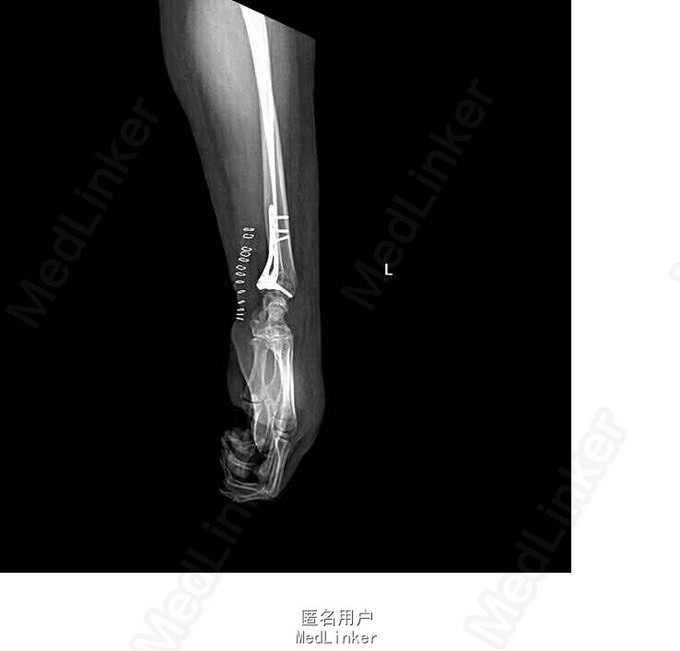

诊断:右侧桡骨远端骨折(barton骨折) 双手皮肤软组织挫伤 行左桡骨远端骨折切开复位内固定术

术后恢复良好